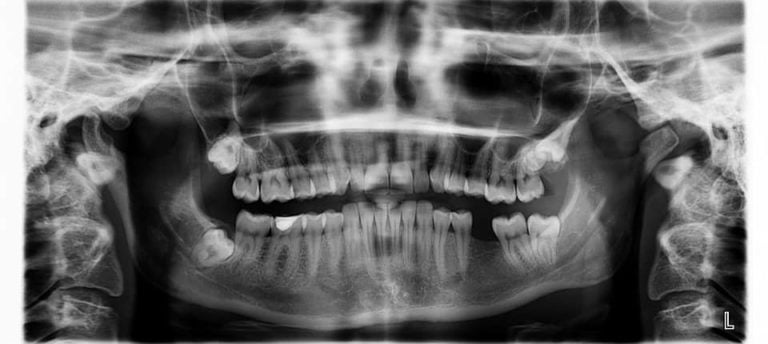

Opg x-ray

A dental X-ray is used for diagnosis, treatment, and follow-up dental problems. Panoramic x-ray helps in examining the dentist those parts with can’t be visible to the naked eye, such as underlined gums conditions, tooth